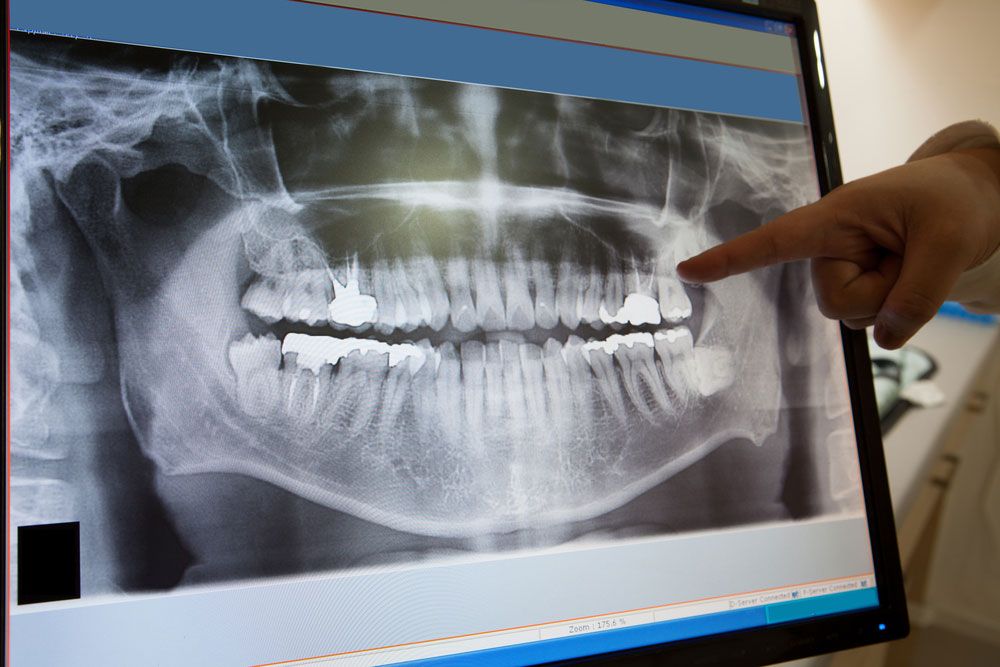

Dental Radyoloji

Diş tedavilerinde teşhisin konulabilmesi ve tedavi sürecinin belirlenebilmesi için dental radyoloji gereklidir.Dijital sistemin kullanılması görüntü kalitesini arttırmak ve hastalarımızın aldığı radyasyon miktarını belirgin şekilde azaltmaktadır.

Diş ve ağız sağlığı için radyografi çok önemli bir yere sahiptir.Dental radyografi ile muayenede fark edilemeyen çürük, kemik kaybı ve kök kanalındaki problemler kolayca tespit edilebilmektedir. Ayrıca röntgenler ortodontik tedavi ve implant yerleştirilmesinde diş hekimlerine yardımcı olurlar.